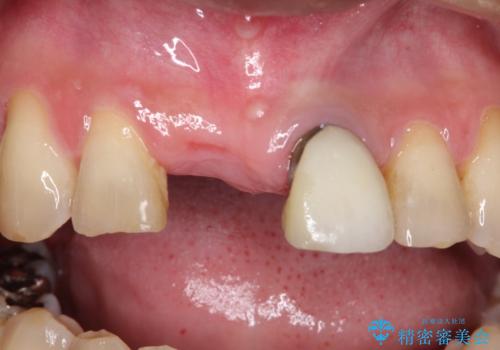

- 矯正治療終了後の患者様です。

前歯が欠損しており、ブリッジでの修復を希望されましたので、オールセラミッククラウン(スタンダード)で治療を行いました。